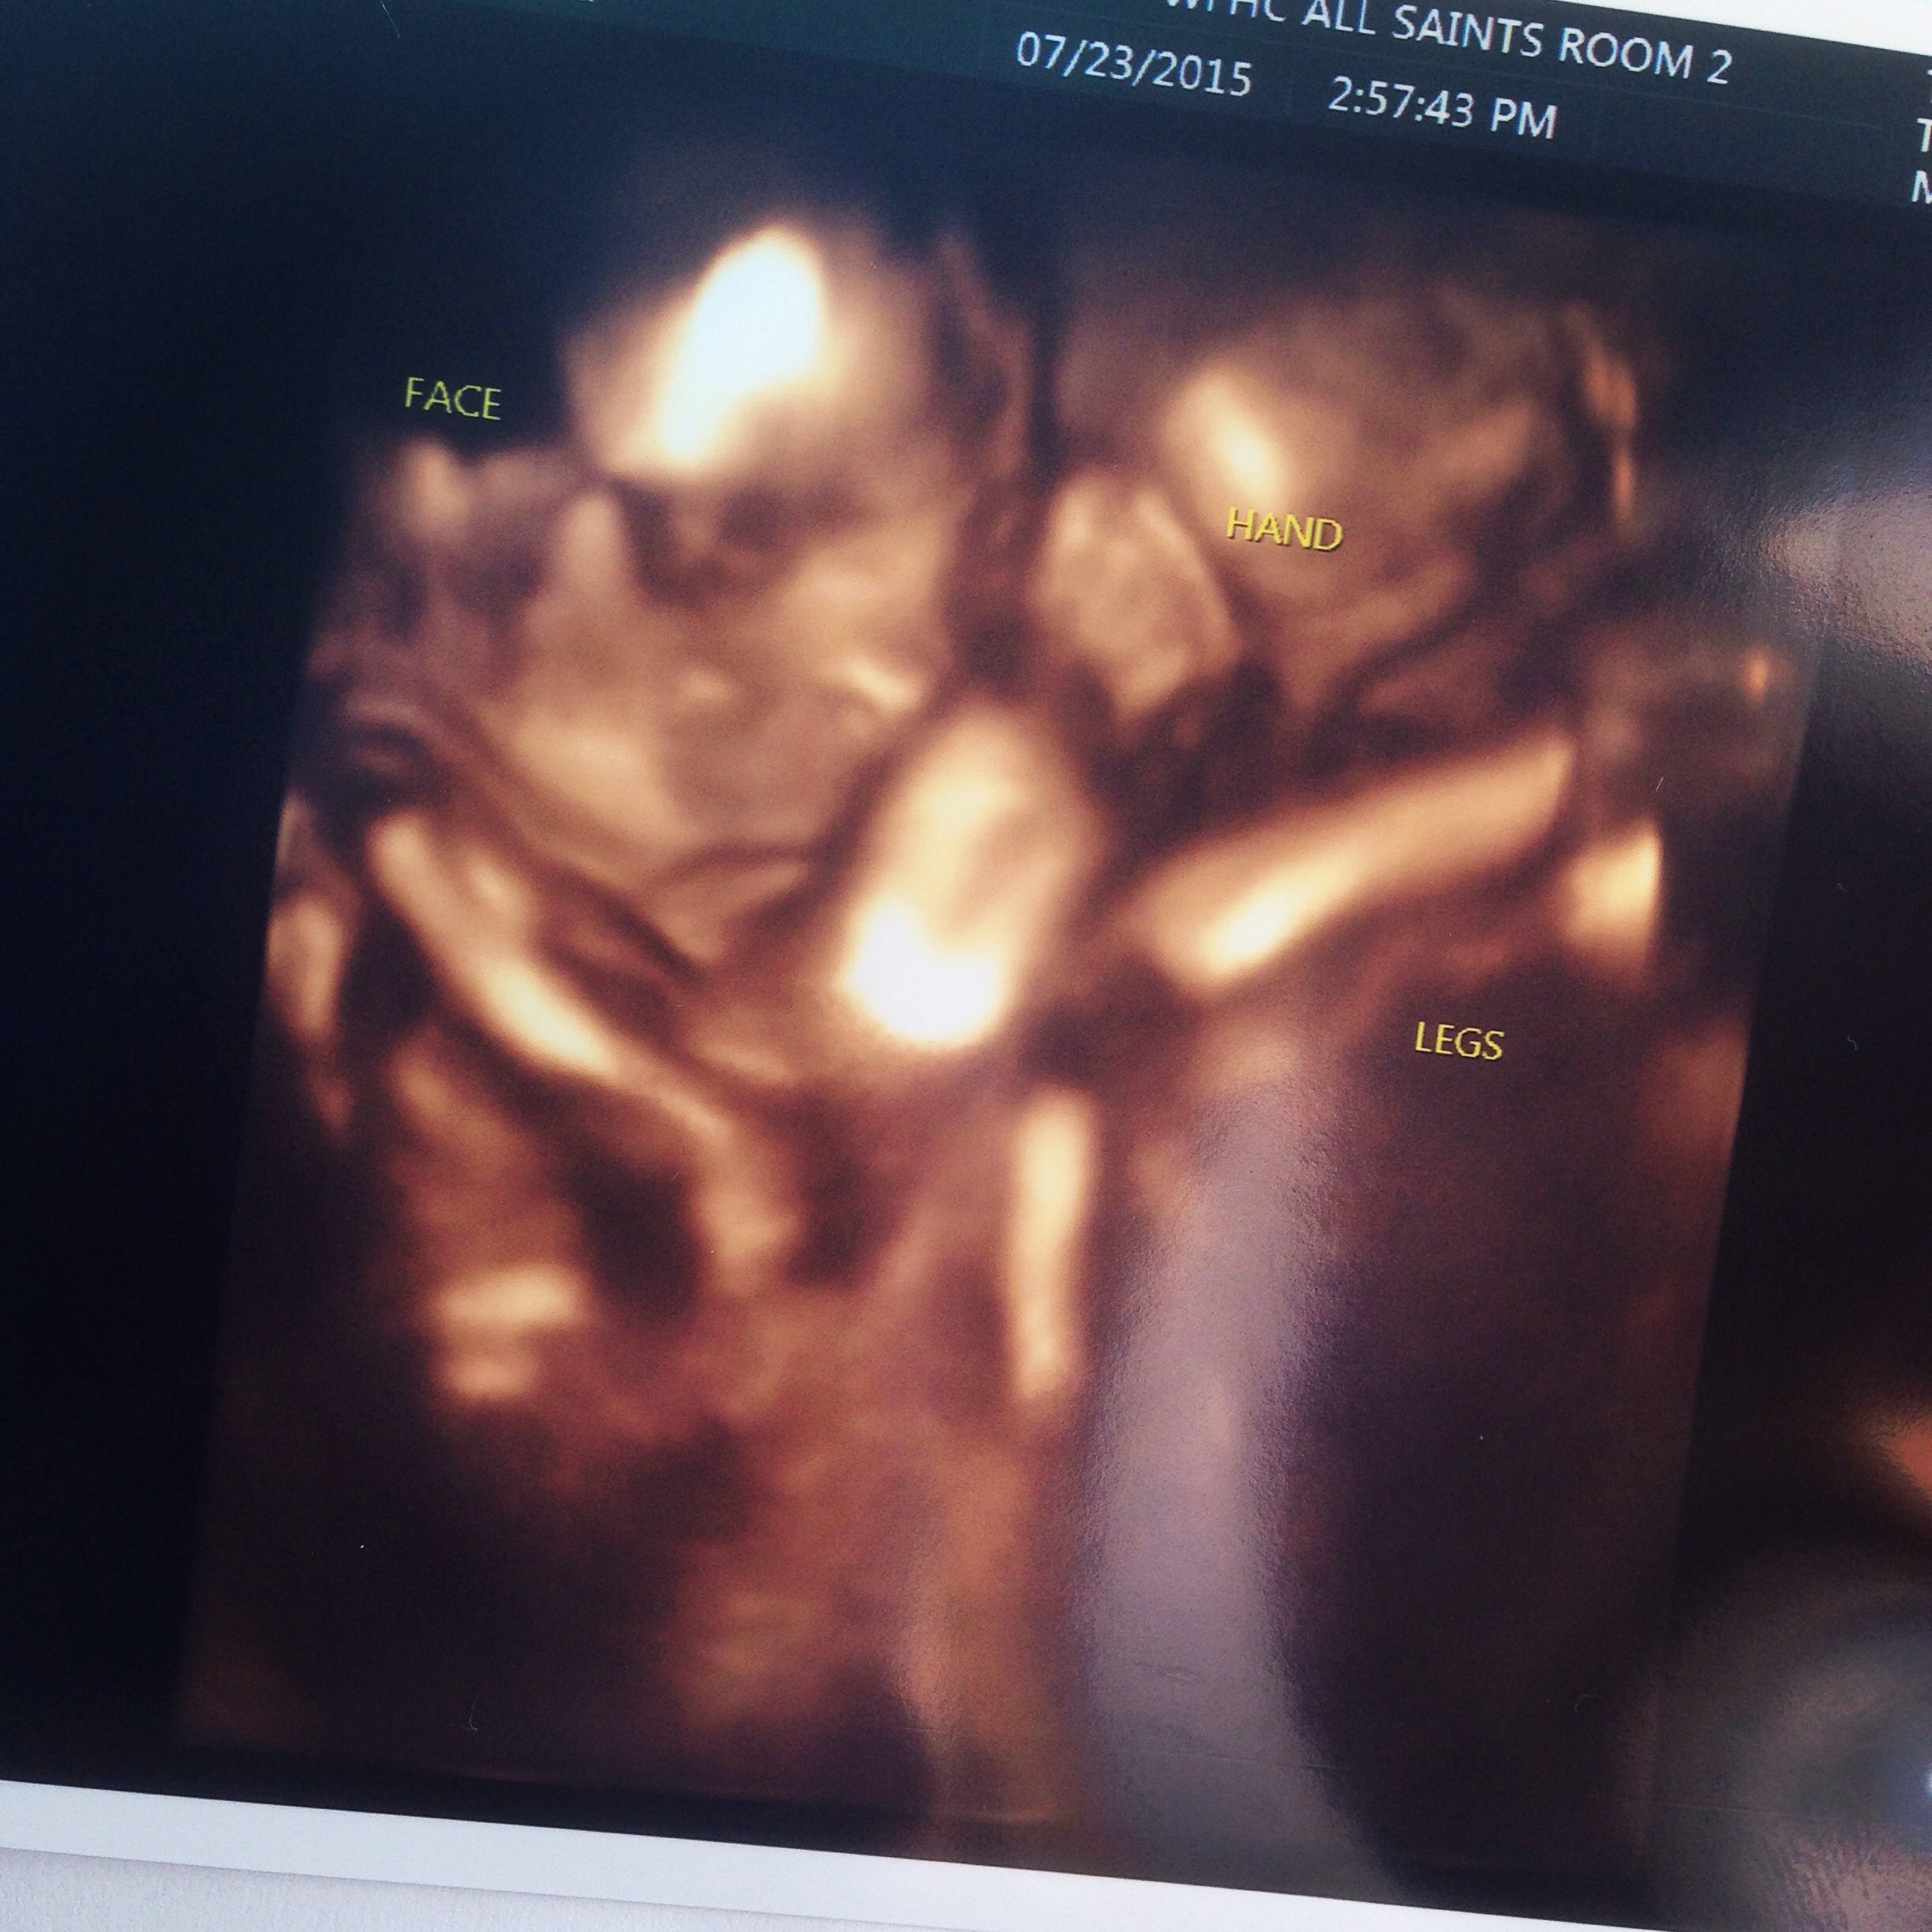

TEAM BLUE GOES HERE!